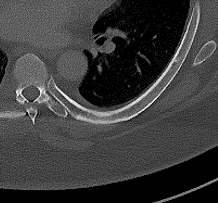

Figure 2: Qualitative results of bone lesion detection. Each column shows a cropped slice with the top row displaying ground-truth (green) and the bottom row showing nnUNet predictions (yellow). (a) shows a TP osteolytic lesion; (b) shows the prediction of a real osteoblastic lesion that was not prospectively marked as ground-truth (before review), and after GT review, it was correctly considered as ground-truth; (c) shows an osteolytic lesion not annotated in ground-truth before review and correctly marked afterwards. A FN adjacent to it is also shown. (d) shows a rare FP on the cortex of a rib.

Results. Qualitative and quantitative results of our model are presented in Fig. 2 and Table 1 respectively. Our model achieved a precision of 96.7% and a recall of 47.3% for detection of bone lesions (lytic, blastic, and mixed). We observed that the model was very confident in its predictions as demonstrated by the vast number of actual lesion predictions (TPs) compared against the FPs. Despite the high precision, the model was not very sensitive to the detection of bone lesions due to the large number of FNs.